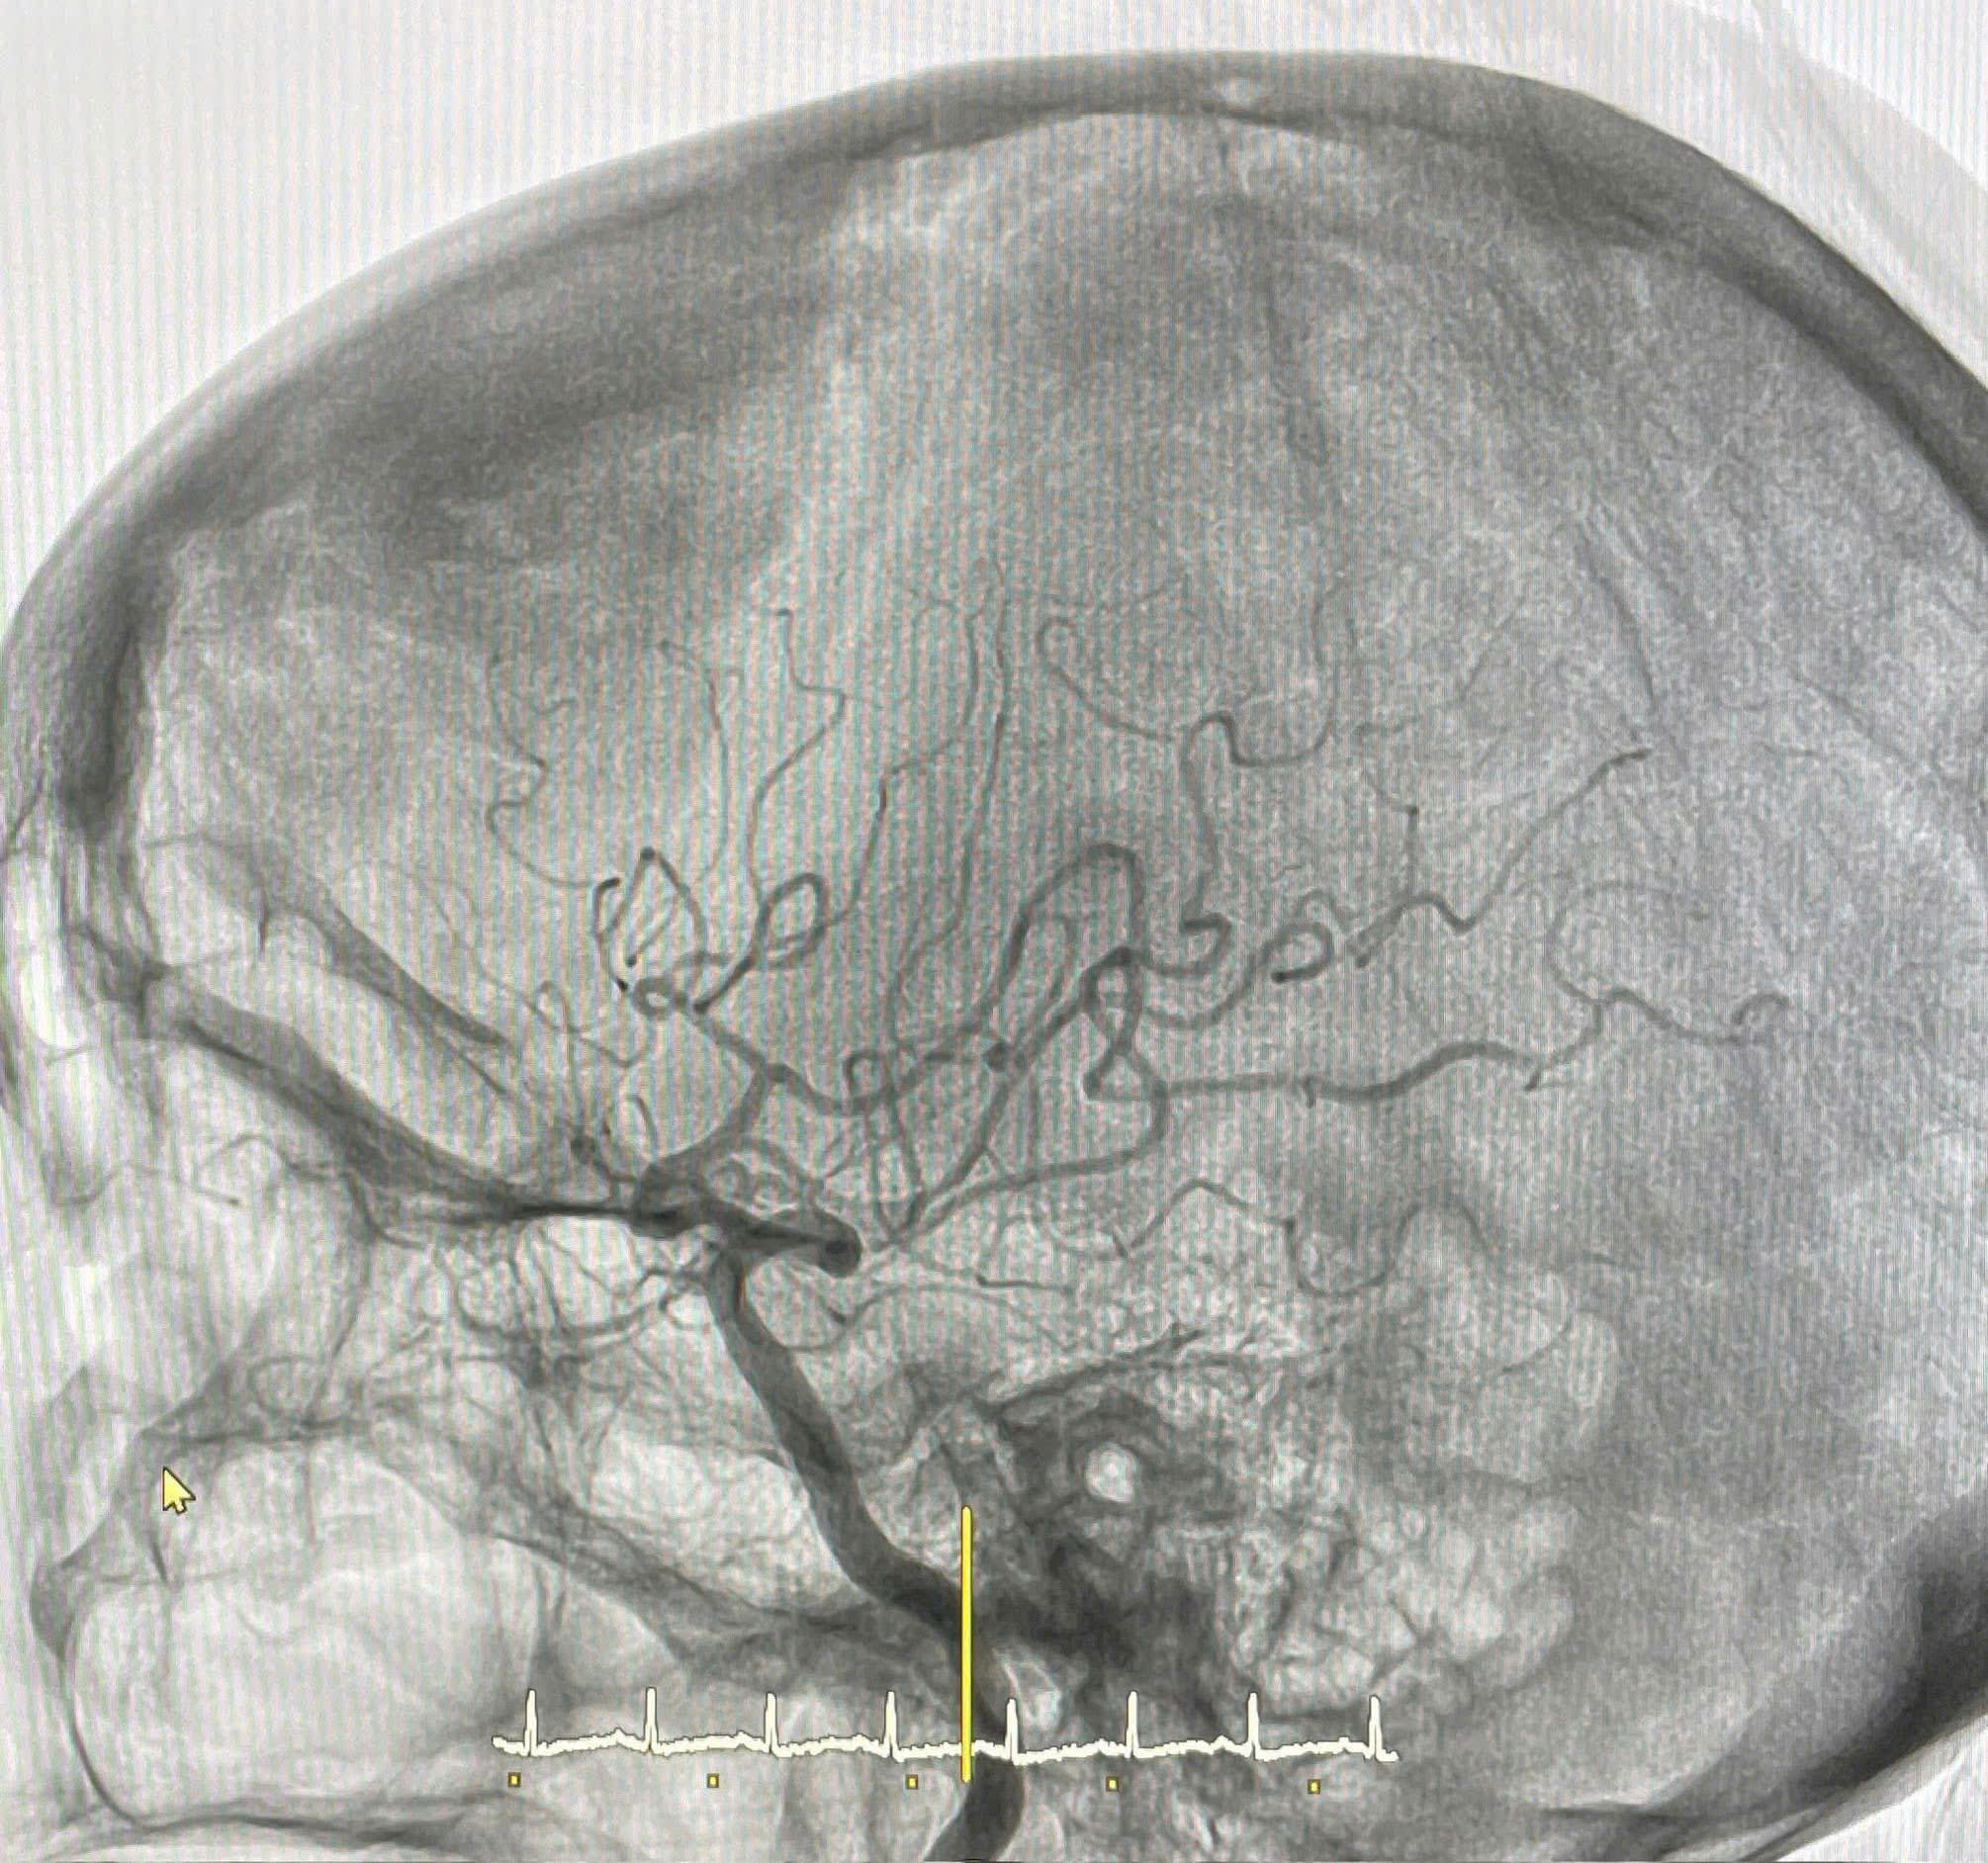

Trước tình trạng tắc mạch nghiêm trọng, bệnh nhân được chỉ định can thiệp tái thông cấp cứu. Ê-kíp can thiệp mạch đã tiến hành chụp mạch não, phát hiện huyết khối gây tắc hoàn toàn động mạch não giữa phải đoạn M1. Các bác sĩ nhanh chóng thực hiện hút huyết khối, tái thông hoàn toàn mạch máu và khôi phục dòng chảy phía sau vị trí tắc.